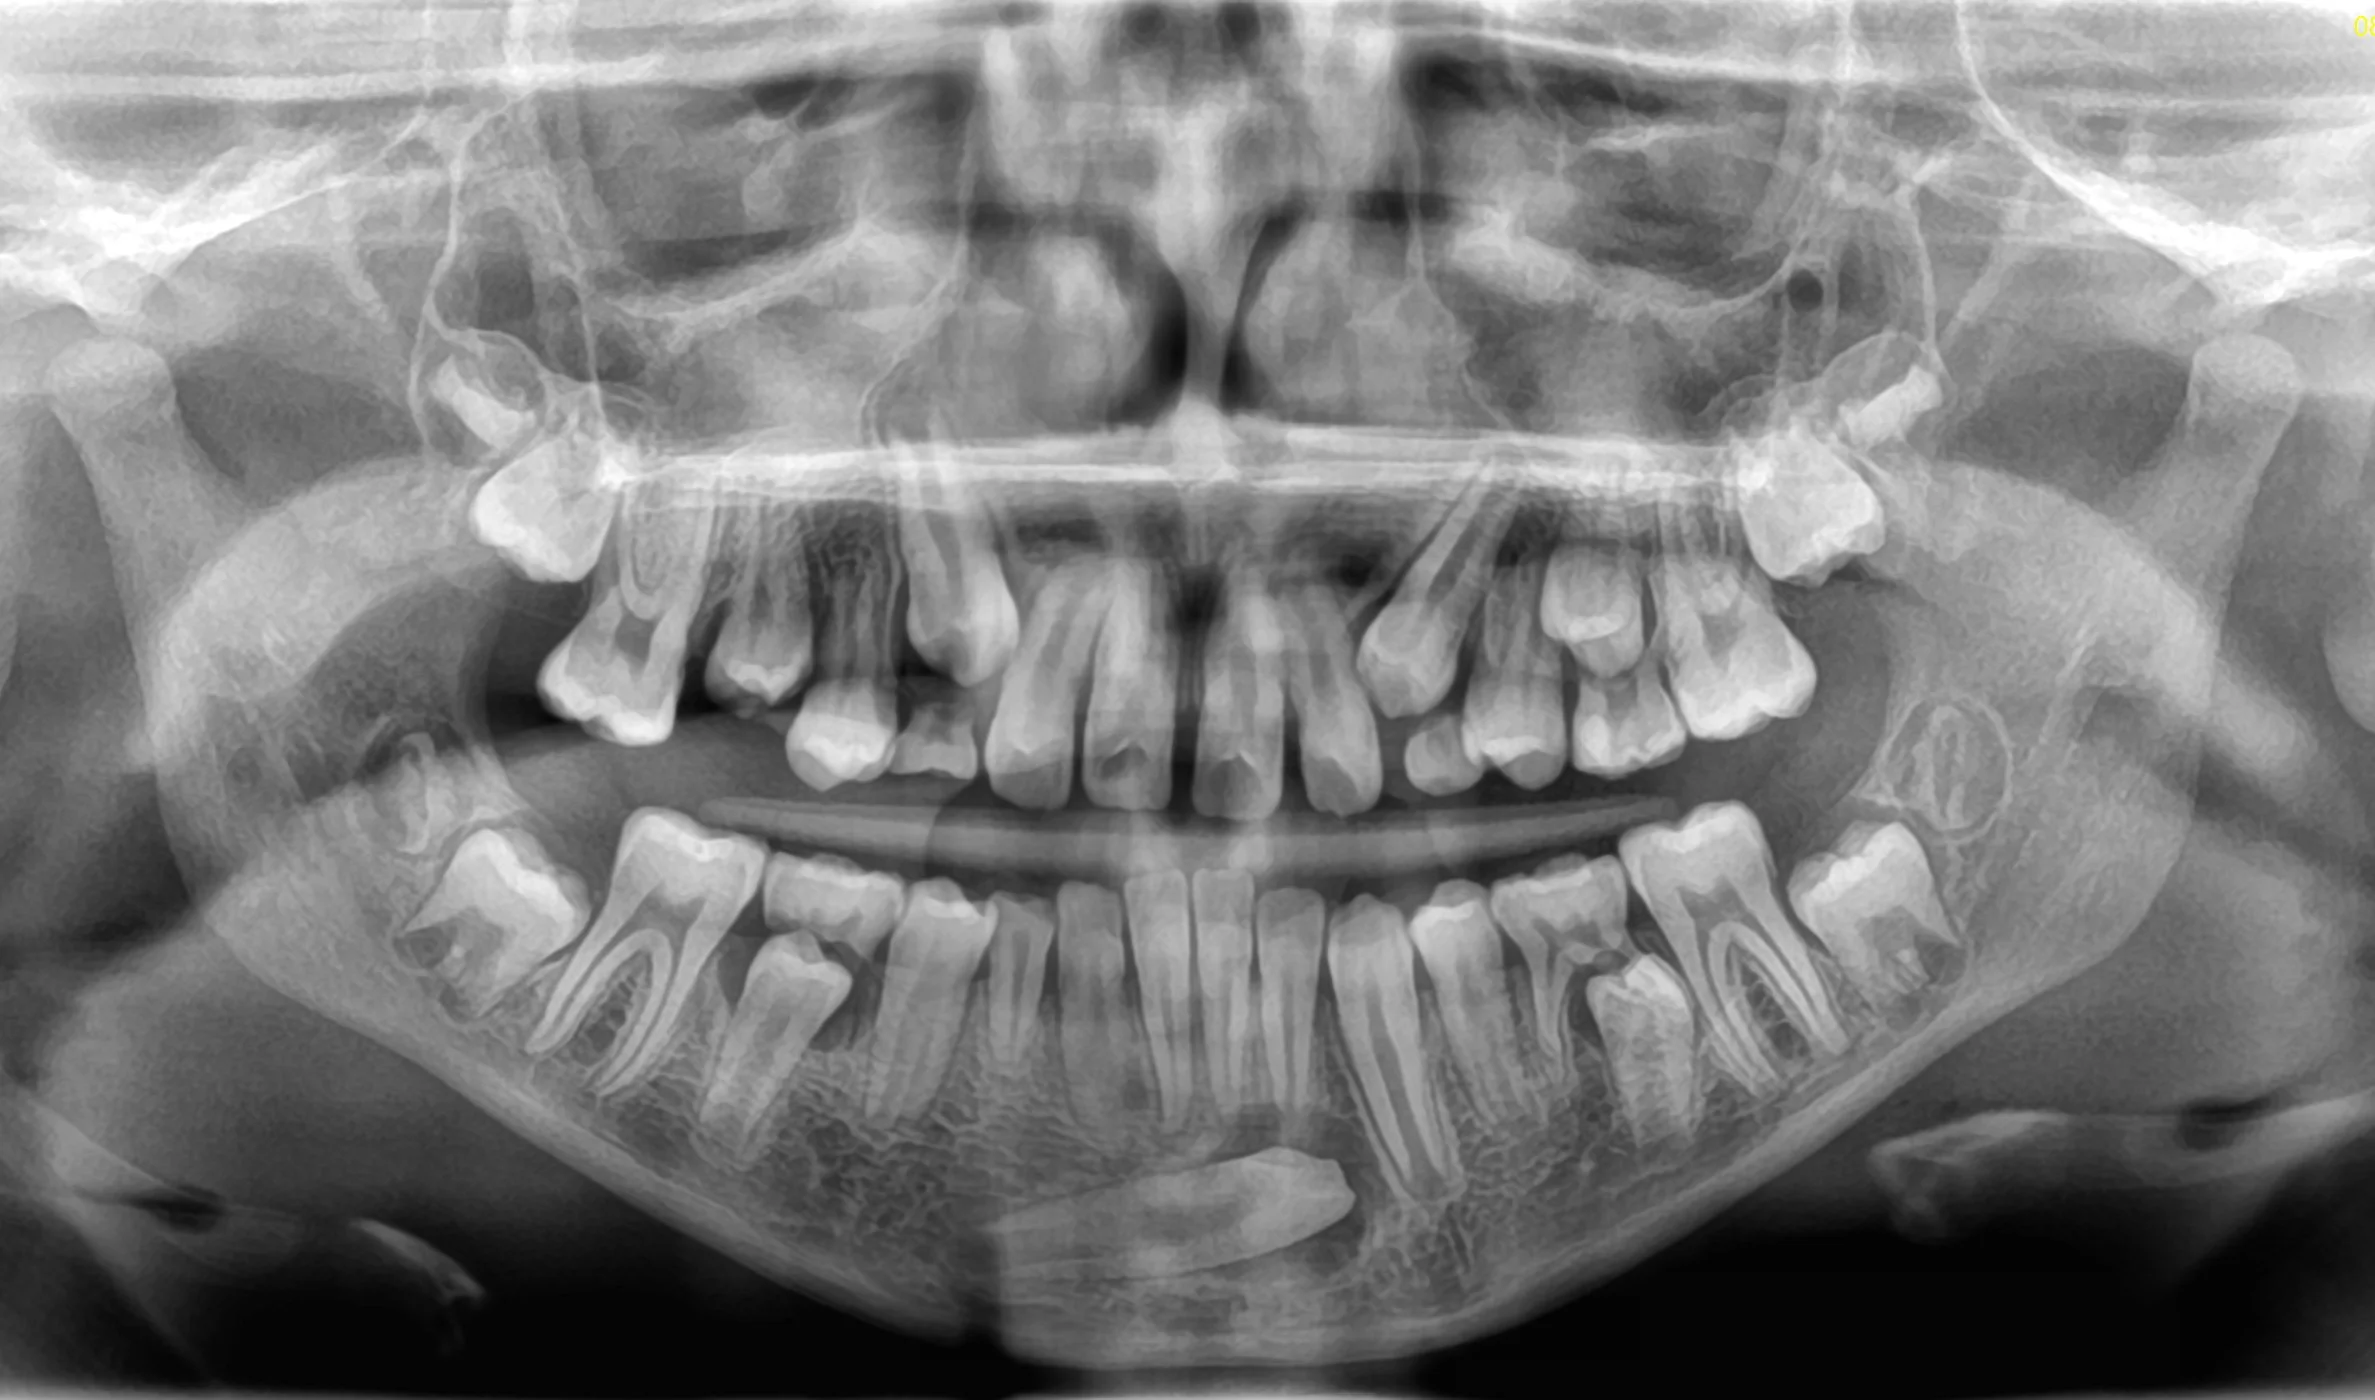

CASO 1

Estrazione di tutti e 4 i denti del giudizio per disodontiasi. Operazione chirurgica avvenuta in due sedute.